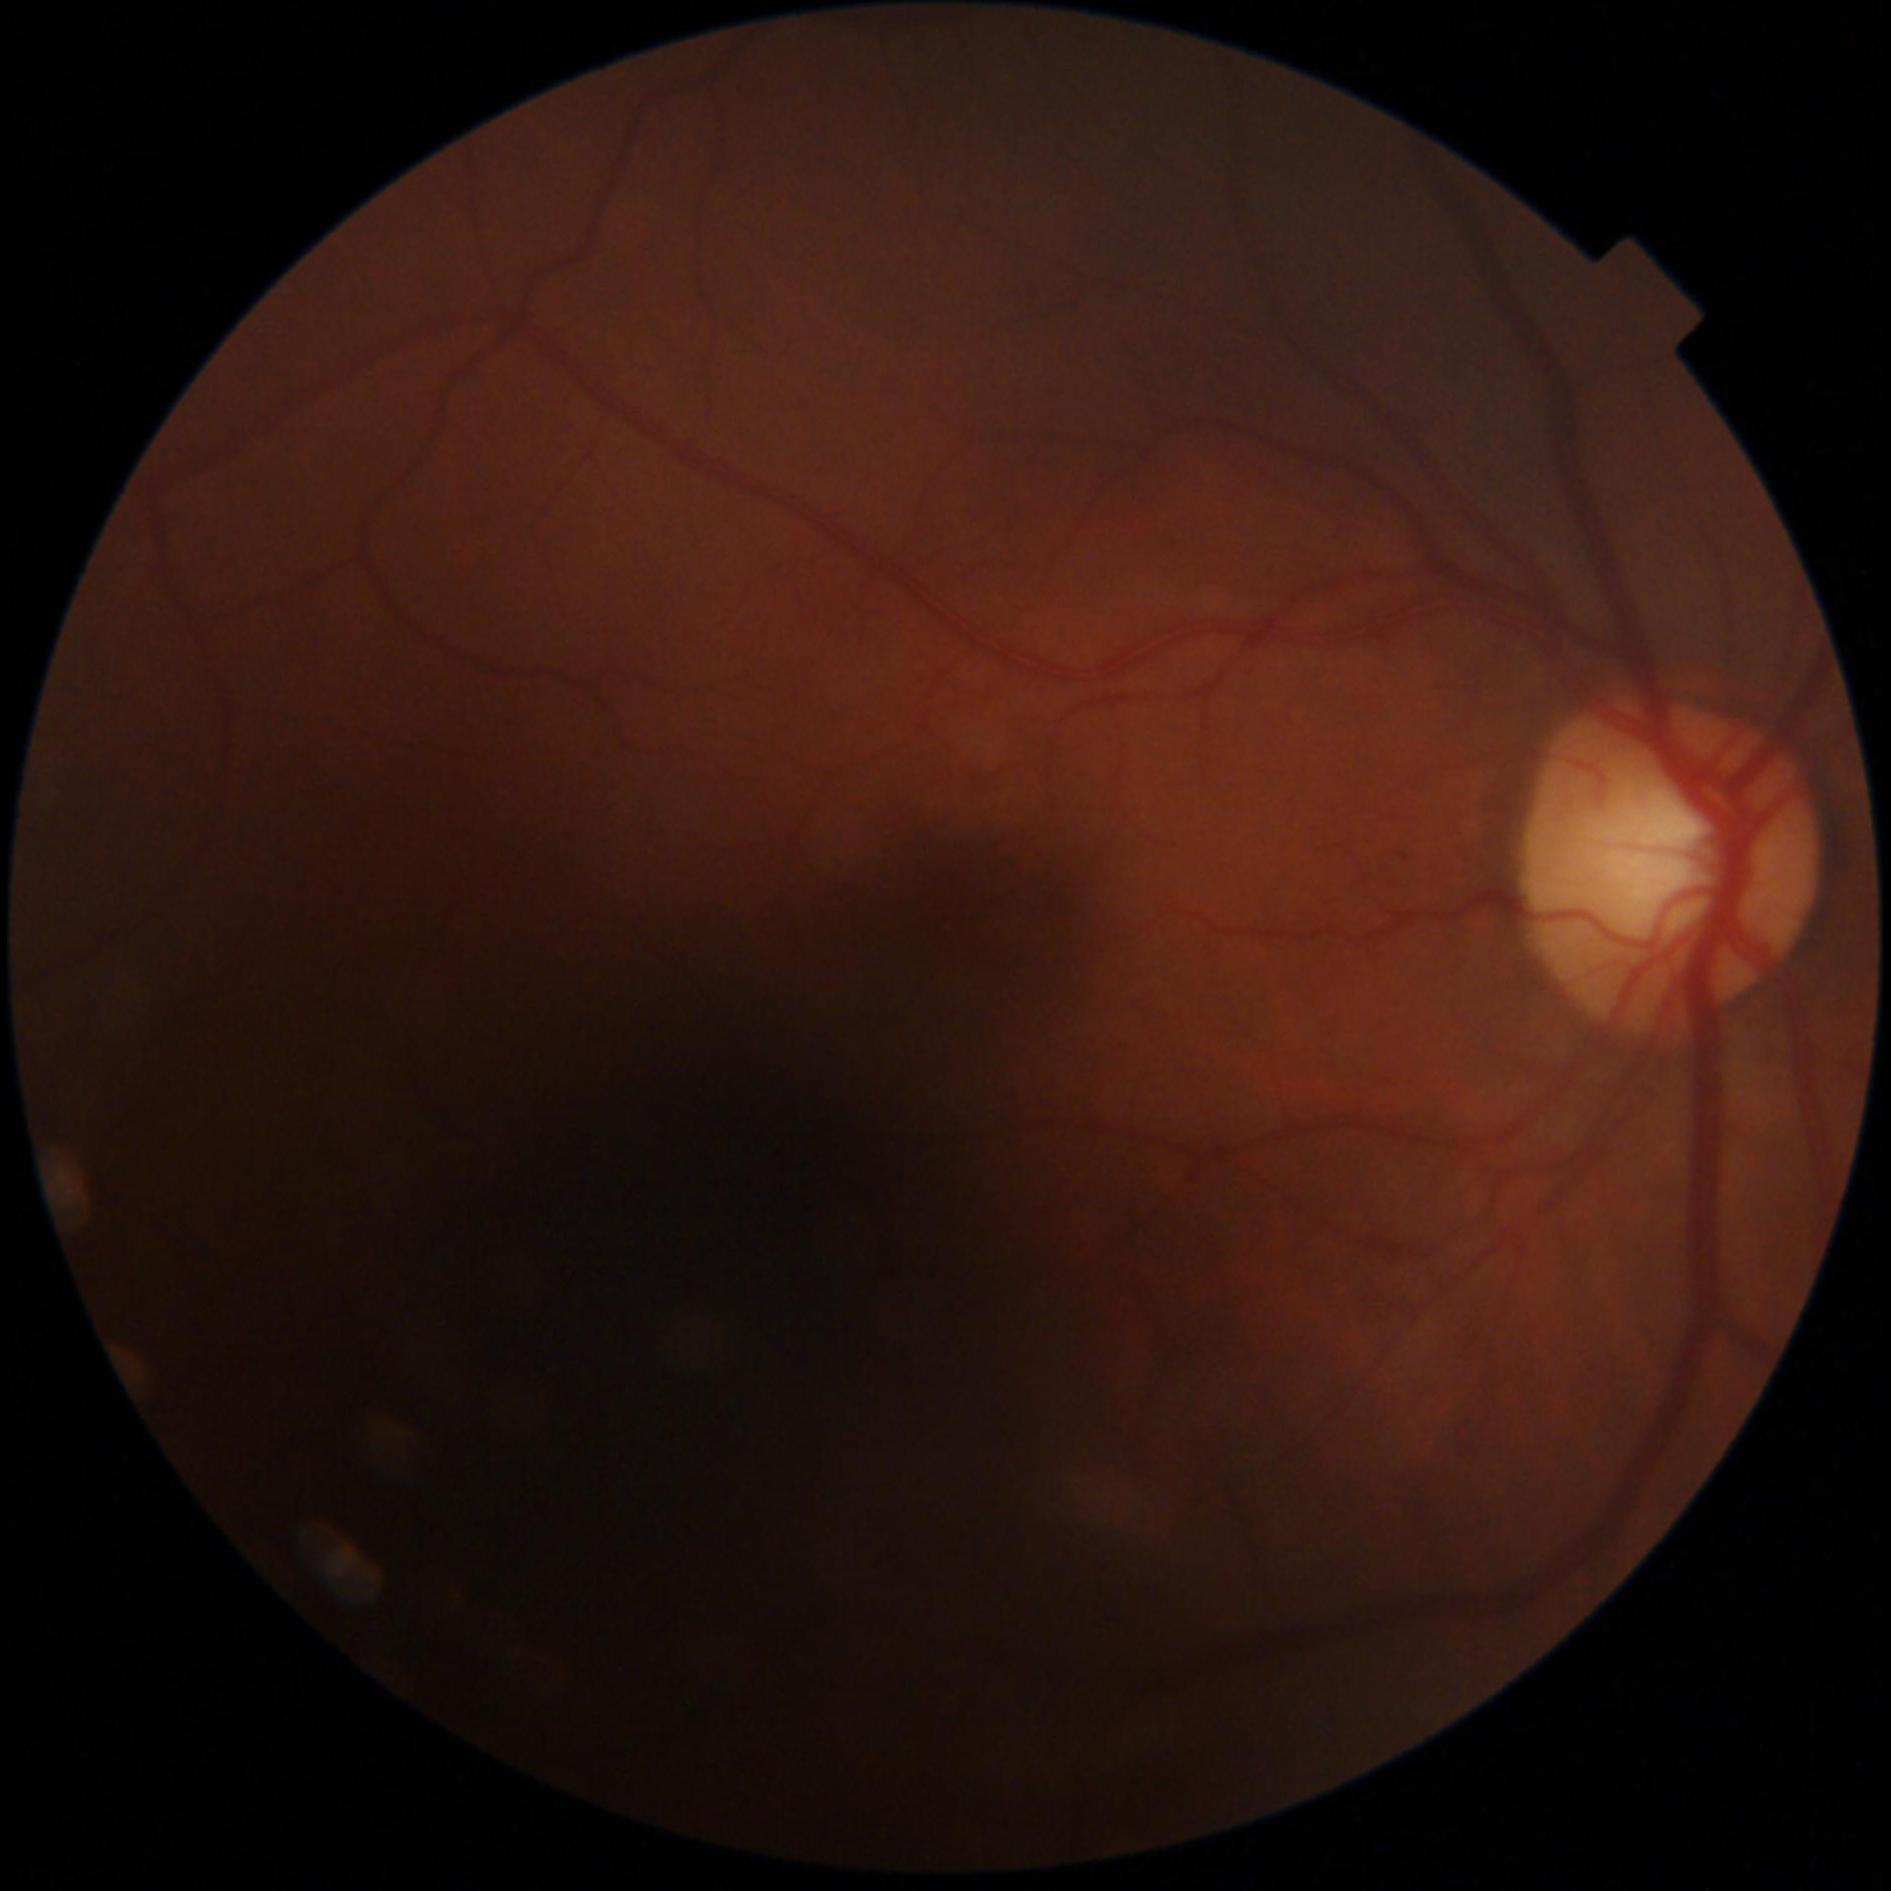

GON is diagnosed through a comprehensive ophthalmic examination that includes intra-ocular pressure (IOP) measurement, anterior chamber and angle assessment, optic disc (OD) inspection, visual field assessment, and optic nerve head imaging [1, 4]. Although effective, these procedures require the expertise of an ophthalmologist and access to specialized, often costly, equipment, which can be a limiting factor. Alternatively, computer-aided analysis of digital fundus images (DFI) can be used to identify GON. DFIs are captured using a fundus camera, which photographs the posterior segment of the eye and provides a clear view of the OD [5].

Recent studies have increasingly utilized deep learning (DL) models for automated GON detection using DFIs [6–8]. However, a major limitation in published research is that GON reference labels are often derived solely from DFI evaluations rather than comprehensive ophthalmic examinations [9–12]. This approach intrinsically reduces the GON detection task to a subjective evaluation of the OD, which has inherent limitations in identifying GON. Consequently, DL models trained exclusively on DFIs may inherit biases, be influenced by subjective interpretations, and inconsistent annotations, include examples that are not verified and potentially diverge from the true clinical manifestation of GON. Additionally, this method can be error prone, since other ophthalmic conditions may mimic the appearance of a GON cupped optic disc, such as ischemic optic neuropathy and compressive optic neuropathy [13].

The dataset was curated by the Hillel Yaffe Ophthalmology Department Glaucoma Unit, Hadera, Israel, between 2022-2024. DFIs were captured using a TOPCON DRI OCT Triton retinal camera with a 45° FOV. The dataset includes subjects aged 36 to 95 years, with 73% of the DFIs classified as glaucomatous. Patient selection followed specific inclusion and exclusion criteria to ensure data quality and clinical relevance.

All DFIs were deidentified, ensuring that any personal identifiers were removed. To maintain consistency, images were cropped to a square format by removing black borders. A quality score for each DFI was computed using FundusQ-Net [5] and is included in the dataset.

The dataset consists of 747 DFIs, including:

- 548 glaucomatous DFIs (73%)

- 199 non-glaucomatous DFIs (27%)